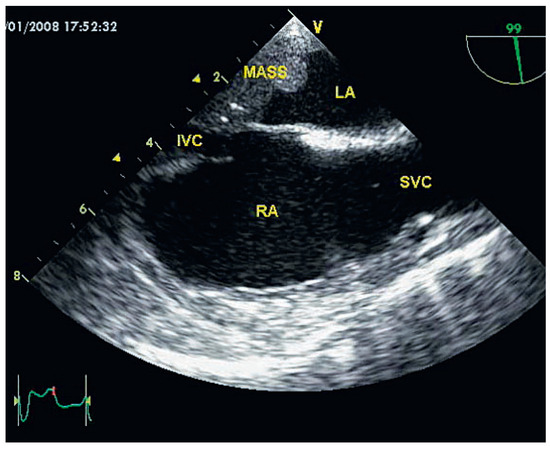

Interesting Images

Benign Left Atrial Glomangiopericytoma

by Michel Grobéty, Gregory Katchatourov, François Perret, Stephan Schäfer and Jean-Jacques Goy

Cardiovasc. Med. 2008, 11(9), 288; https://doi.org/10.4414/cvm.2008.01347 (registering DOI) - 26 Sep 2008

Cited by 1 | Viewed by 100

Abstract

Case report This 47-year-old woman had a history of Hodgkin disease treated with chemotherapy and irradiation at the age of seventeen [...] Full article

Show Figures

Figure 1